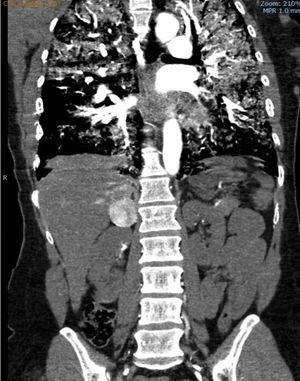

Presentamos el caso de una mujer de 41 años sin antecedentes de interés que consulta por un cuadro de 24 horas de evolución de malestar general, cefalea y palpitaciones. A su llegada a urgencias presentaba emergencia hipertensiva (180/100), clínica de hipoperfusión con hiperlactacidemia e insuficiencia respiratoria hipoxémica. Mediante TAC toraco-abdominal se objetivó una ocupación alveolar bilateral y una lesión hipercaptante en fase arterial en la glándula suprarrenal derecha de 4cm (fig. 1). En el ecocardiograma presentaba una hipoquinesia grave del ventrículo izquierdo (VI) respetando los segmentos apicales y una fracción de eyección (FE) del 17% (video 1).

En situación de shock cardiogénico y disfunción multiorgánica, con necesidad de ventilación mecánica invasiva y soporte con noradrenalina y dobutamina a dosis altas se trasladó a nuestro centro, donde se implantó una ECMO venoarterial (VA) femoro-axilar de forma emergente. Tras ello mejoró la disfunción multiorgánica y se retiraron totalmente las aminas, quedando la paciente con tendencia a la hipertensión arterial. Se solicitaron catecolaminas en orina (metanefrinas y normetanefrinas) que superaban 10-20 veces el valor de referencia, y se revisó la TAC confirmándose el diagnóstico de feocromocitoma (FC).

El curso clínico de hipertensión arterial y disfunción sistólica, y la presentación ecocardiográfica atípica orientó a revisar los hallazgos de la TAC que fue el método diagnóstico de FC. El estudio de catecolaminas en orina suele tardar varios días o incluso semanas lo cual supone un retraso inviable en casos extremos como fue nuestro caso.